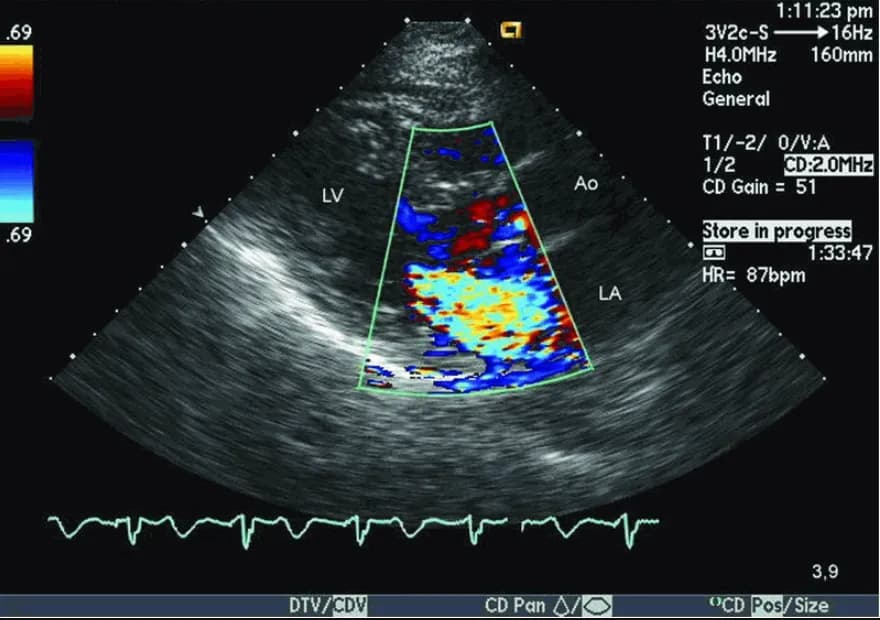

- Siêu âm tim: Siêu âm tim là một xét nghiệm quan trọng để chẩn đoán kênh nhĩ thất toàn phần. Nó có thể cho thấy các bất thường về cấu trúc của tim, bao gồm khuyết gối nội mạc (một dấu hiệu đặc trưng của kênh nhĩ thất), thông liên nhĩ và/hoặc thông liên thất, hở van hai lá và/hoặc van ba lá (do chẻ lá van hoặc thiếu mô van), tăng áp phổi (nếu có), giãn các buồng tim và giảm chức năng co bóp của cơ tim.